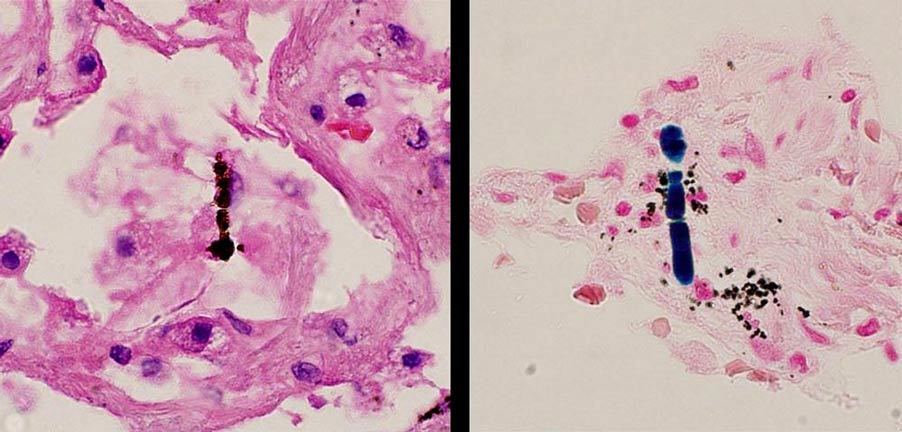

The material shown in the figure is an asbestos fiber that has been coated with iron (ferruginous body). The beaded appearance is due to the layering of an iron rich coating around the relatively thin, needle like fiber. Such a finding is indicative of prior asbestos exposure but does not indicate that the decedent has an occupational lung disease (asbestosis) or mesothelioma.